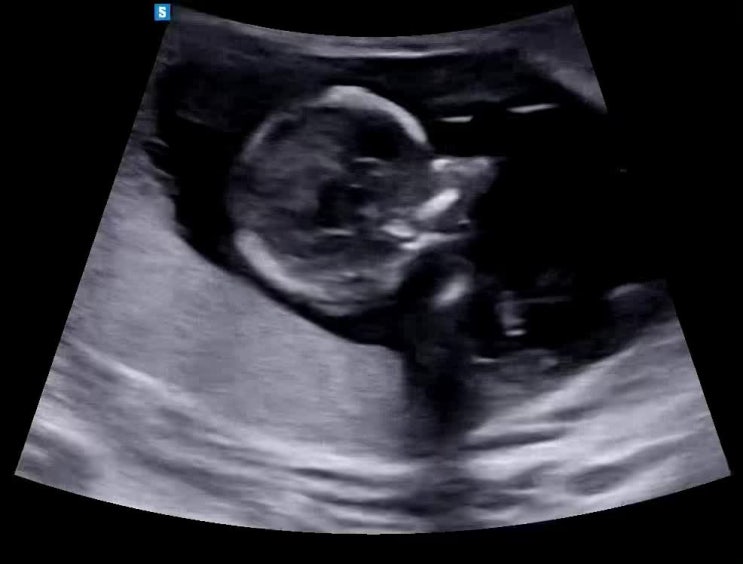

[임신 기록-⑧증상기록] 임신 13주 차 증상 기록 / 임신 초기 증상 / 1차(초기) 기형아 검사 진행

부산양양이의 소확행♪ 오늘은 임신 13주 차 증상 관련 포스팅을 해보겠습니다 : ) 오늘은 1차 기형아 검사...